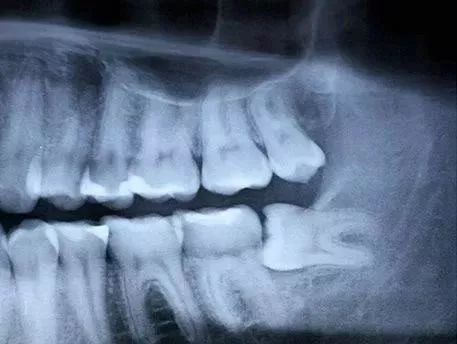

有条件的就选择微创拔牙,传统拔牙是以“锤、劈、敲”等方式进行,近几年随着口腔外科微创理念的不断发展,拔牙技术和器械的不断革新,微创拔牙应运而生,大大减轻患者拔牙时的痛苦。

由于微创拔牙器械的薄而锋利,可以快速而准确地切断牙周膜,保护牙槽骨的完整性,手术损伤小,术后疼痛轻,创口愈合也比传统拔牙后恢复得快。

微创拔牙尤其适合对付各种智齿↓